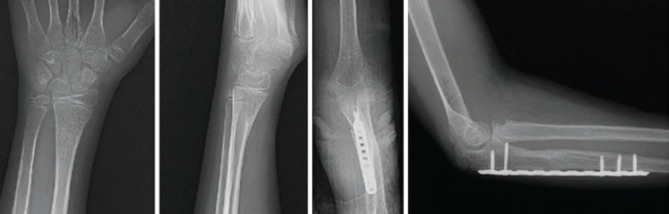

In this case report, we present a 13-years-old patient who sustained a Monteggia equivalent fracture along with an ipsilateral distal radius fracture following a fall on the elbow. Comminuted ulnar fracture was treated with open reduction and internal fixation with a bridging plate. After restoring the ulnar length, the radial neck fracture was successfully reduced. The distal radius fracture was managed conservatively. Our literature review shows that, the patient is one of the comparatively older patients treated with open reduction and internal fixation in this area and that a successful outcome was achieved with early mobilisation. This case underscores the need for further studies to determine the optimal treatment strategy in such cases.